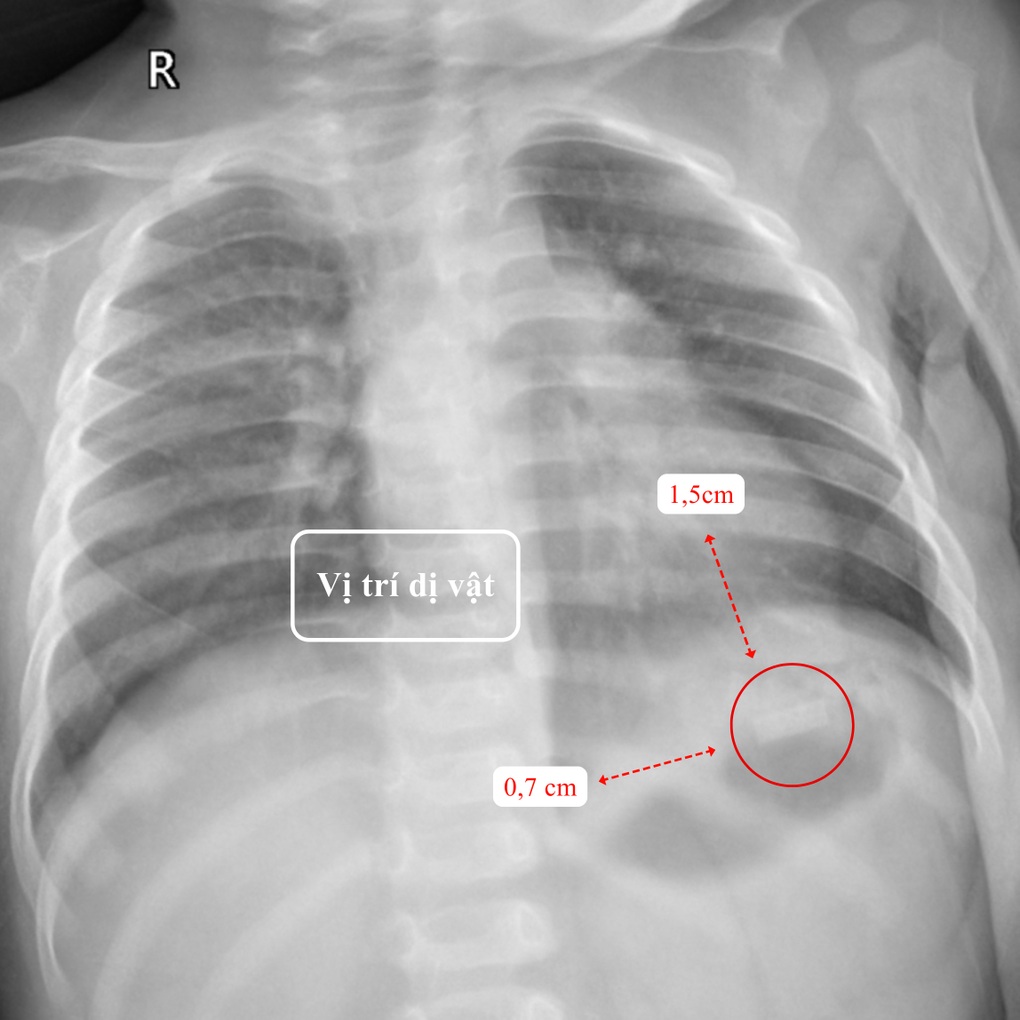

Tại Khoa Nhi - BVĐK Hồng Ngọc - Phúc Trường Minh, kết quả thăm khám lâm sàng và cận lâm sàng cho thấy một dị vật kim loại hình chữ nhật kích thước 1,5x0,7cm, có góc nhọn, mỏng và sắc như lưỡi dao nằm tại vùng hạ sườn trái, vị trí bóng hơi dạ dày của bé T. Ngoài ra, do nuốt phải một phần thuốc lá, trẻ có biểu hiện say thuốc với triệu chứng mệt mỏi, môi tái.

Vị trí dị vật trên phim chụp X-quang (Ảnh: BVCC).